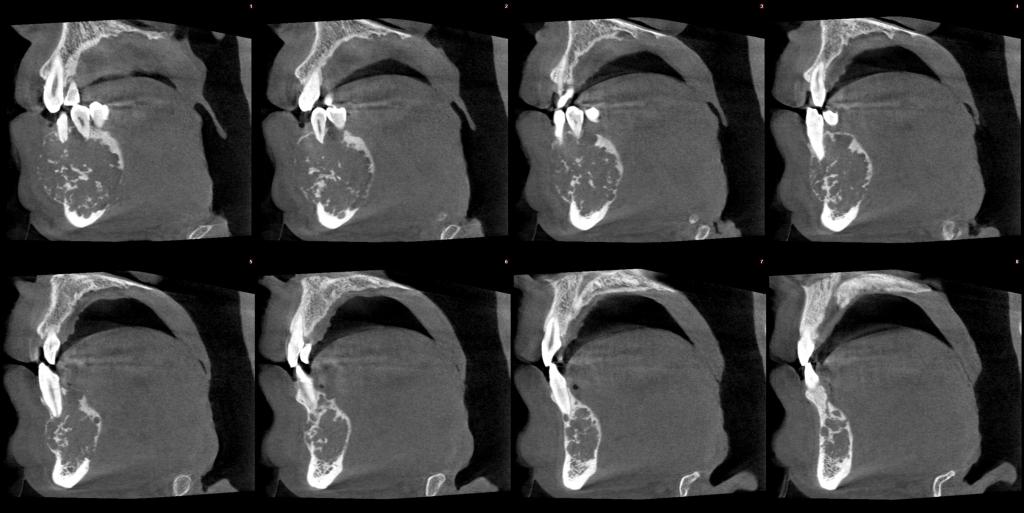

常规开展:数字化根尖片/横断牙合片、数字化口腔曲面体层片、头影测量侧位/正位片、手腕骨片、颅颌面CBCT、牙齿CBCT的检查以及涎腺造影、窦道 瘘管造影。

颅颌面CBCT

诊断范围涉及牙体牙髓病、牙周病、阻生牙/多生牙定位、种植牙术前CT评估分析、颞下颌关节CT诊断分析、,颌骨及涎腺疾病、颌面发育畸形、正畸治疗辅助诊断等大部分颌面部疾病,为临床医疗提供强有力的支持。